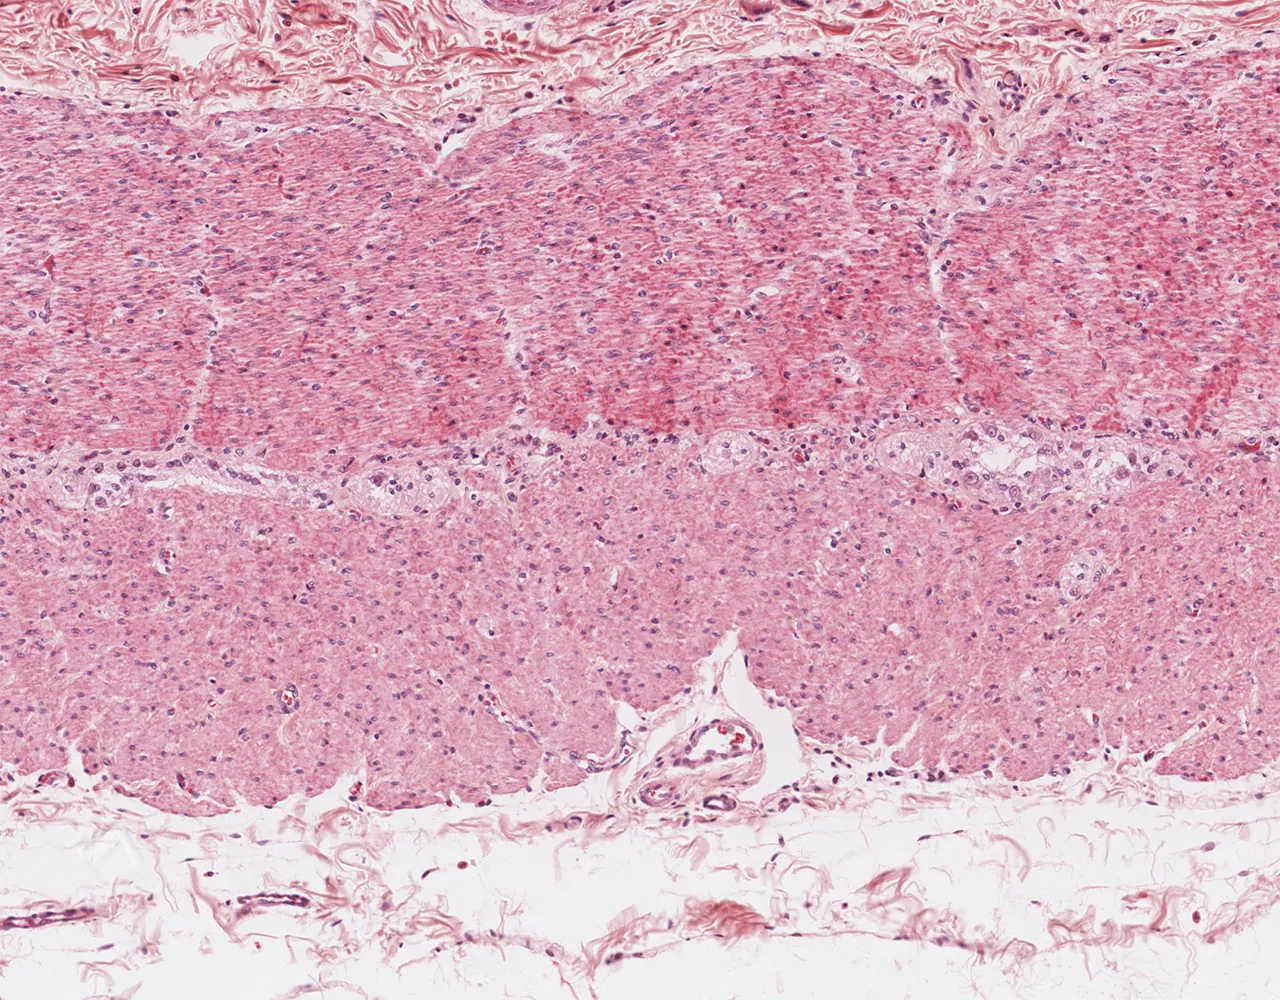

- The absorptive surface area of the small intestine is amplified by three structural levels: plicae circulares, villi, and apical microvilli forming the brush border.

- Microscopically, the wall is composed of 4 layers from the inside outward: mucosa, submucosa, muscularis propria, and serosa.